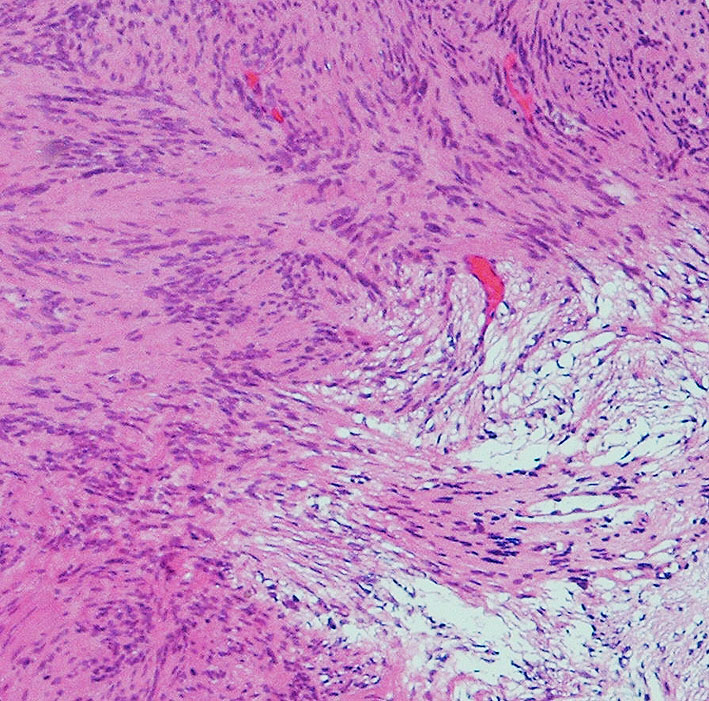

細胞核の柵状配列 (矢印 nuclear palisading). HE x200

画像をクリックすると拡大します

細胞核が円状に並んだ形態で、いわゆるVerocay bodyと呼ばれる所見(矢印)。 HE x200.

隣り合う細胞核の柵状配列 nuclear palisade arrangement (palisading) は,髄膜腫との鑑別での大切な所見です。